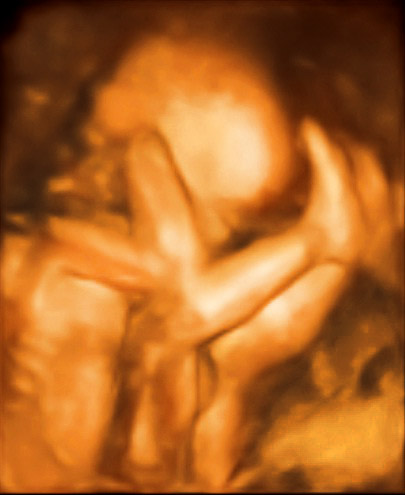

5/8小寶的第20週也是我們第二次去榮總產檢。

這次是照高層次超音波和4D的影像,

雖然這部分需要自費(兩種加起來2500元),也不是必要性的檢查,